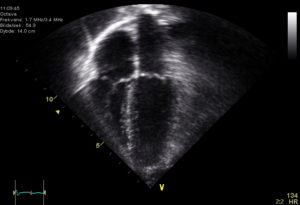

As discussed previously here, those with congenital heart disease have to follow up with clinicians for the rest of their lives. A typical follow up has the patient receiving an echocardiogram. During an echo test, ultrasound from a hand-held wand allows for the assessment of the overall function of the heart, and evaluation of the progression of treatments or disease. During this test other aspects of the heart, such as blood flow and heart rhythm can be observed.